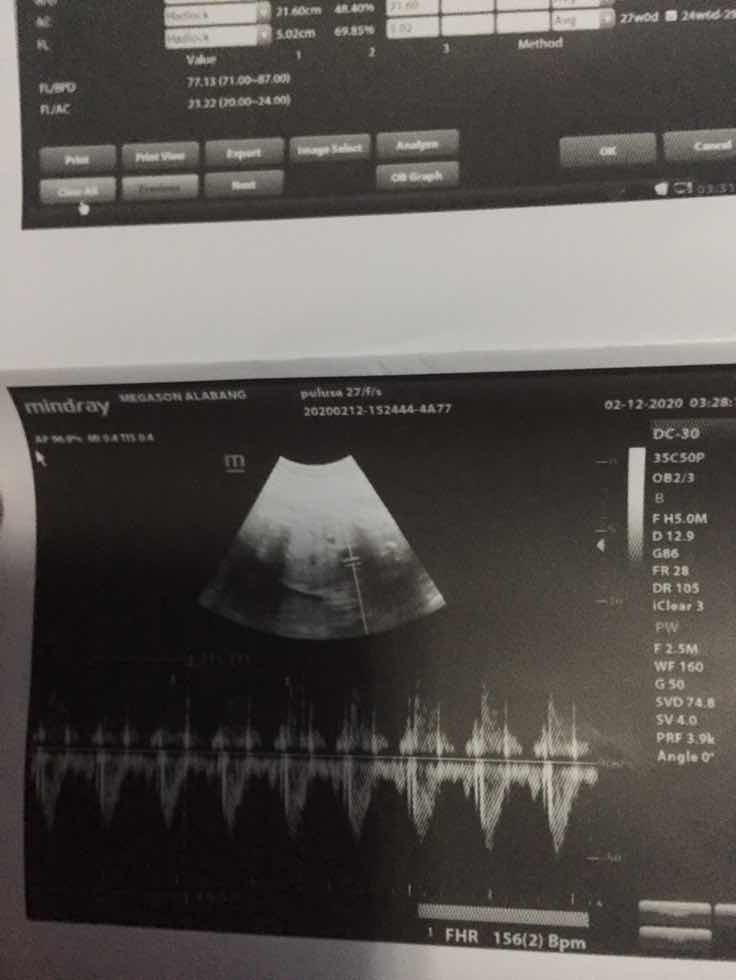

Sa sobrang excited ko .. nag pa Ultrasound ako 5mos .. pero hindi nakita ... anu kayang gender ng anak ko?? TIA ??